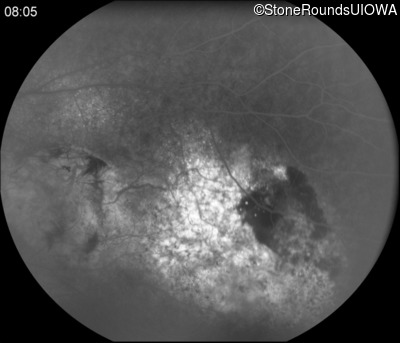

Infrared Fundus Photograph - Right - 20/160 -2

Exemplar